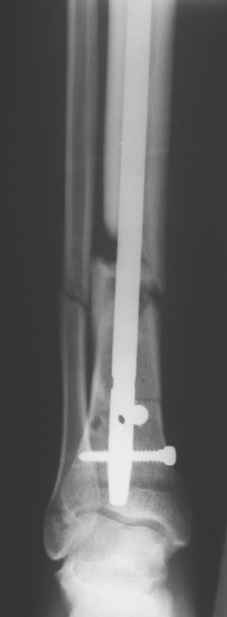

Сегодня прооперировали без открывания. Хотел-бы услышать комментарии по поводу послеоперационной нагрузки.

С уваженем, Ю.А.Булахтин

Учитывая изначальные снимки и то. что сделали , не открывая - весьма достойно. Доктор Коган прав - перелом немного перерастянут ( что хорошо видно по фибуле), а перерастянутые переломы большеберцовой срастаются очень плохо. Поэтому я бы обязательно дал раннюю динамизацию - на 6 неделях ( когда можно не опасаться малротации) разблокировал бы проксимальный фрагмент полностью и начал бы нагружать ногу. Будьте готовы к остеотомии ( или остеоэктомии участка) малоберцовой чеерз несколько месяцев- уж слишком хорошо стоит - очень вероятно, что срастется рано и будет держать большеберцовую перерастянутой

вдогонку - до разблокирования нагружать противопоказано - все, чего добьетесь - погнете шурупы. причем, если погнете дистальные ( как обычно бывает) - гвоздь провалится в сустав. Нагружайте птолько после проксимальной динамизации, когда будете уверены, что гвоздь поднагрузкой будет смещаться вверх, а не вниз

По представленым снимкам, "контакт" между отломками не очень =(. А боковой проекции нет?

Если "так оставлять", то время начала нагрузки мало повлияет на результат.

Уважаемый Юрий Алексеевич, сложный перелом, смелое решение, хорошее исполнение и, надо надеяться, хороший будет результат. Но, что бы он (результат) был достойным, надо подготовиться и к худшему. В чём, с моей точки зрения, главная проблема, которую придётся решать. Да, вне всякого сомнения, система нуждается в ранней динамизации в совокупности с ранней же нагрузкой. В данном случае, мне кажется, можно было бы решиться и на первичную динамизацию, то есть проксимально блокировать гвоздь только через овальное отверстие, отказавшись от введения винта через круглое отверстие. В этом случае и нагрузку можно было бы начать раньше, чем через 6 недель, не опасаясь перелома дистальных винтов. Однако, имеющееся лёгкое вальгусное смещение может прогрессировать в случае полной нагрузки, которую, как справедливо отмечено форумом, требует имеющееся стояние отломков. И предотвратить дальнейшее вальгирование может достаточная наружная опора, которая возможна при хорошем стоянии поперечного перелома малоберцовой кости даже без его внутренней фиксации, как раз как в представленном случае. А, в то же самое время, раннее сращение малоберцовой кости может препятствовать консолидации большеберцовой кости. То есть, своеобразный замкнутый круг может получиться. И так, главная проблема, с которой мы можем здесь столкнуться зависит не от диастаза между основными фрагментами, и не от вальгуса, и не от хорошей репозиции поперечного перелома малоберцовой кости - а от совокупности всех трёх факторов.

Поэтому, мне кажется, пациент будет требовать постоянного внимания на этапе реабилитации. И, помимо темпа консолидации, контроля положения дистального конца гвоздя из за опасения пенетрации сустава, не меньшего внимания будет заслуживать и угловое стояние отломков. Мне кажется, что в случае отсутствия формирования периостальной мозоли в допустимые сроки вряд ли будет целесообразным выполнение остеотомии малоберцовой кости. Это, равно как и хотя бы незначительное усугубление вальгуса может послужить основанием для переустановки гвоздя. Но - это худший вариант, который, я надеюсь, не случится. Но о котором нужно помнить.

АВ> Однако, имеющееся лёгкое вальгусное смещение

Что-то не то тут с вальгусом. По положению гвоздя не должно его быть.

Увидеть бы сравнительные снимки дистальных отделов голеней, может статься, симметричный голеностопный сустав выглядит так же.

Насчет диастаза - конечно, надо динамизировать хоть сегодня, ждать 6 недель я бы не стал. И боковой снимок бы увидеть.

Выкручивать проксимальный статический винт можно, если еще не выкрутили) Нагрузка - ногу на пол ставить можно, без переноса веса тела на нее. А с вальгусом действительно интересно на снимке выходит, может ротационное смещение осталось? Любопытно на боковую взглянуть и на ногу без рентгена